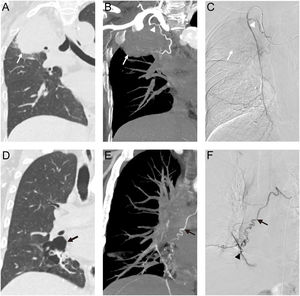

Intraprocedural Angio-CT and confirmatory angiography in a 56-year-old woman with lung cancer-related massive hemoptysis: (A) coronal CT image (lung window) demonstrates a right upper lobe tumor (white arrow). (B) Coronal CT maximum intensity projection image (mediastinal window) reveals an ectopic bronchial artery (white arrowhead) arising from the right internal mammary artery, supplying the tumor (white arrow). (C) Selective angiography image of the right internal mammary artery confirms the culprit artery (white arrowhead) and tumor parenchymal staining (white arrow). Intraprocedural Angio-CT and confirmatory angiography in a 47-year-old man with bronchiectasis-related massive hemoptysis: (D) Coronal CT image (lung window) demonstrates cystic lesions (black arrow) in the right lower lobe. (E) Coronal CT maximum intensity projection image (mediastinal window) reveals a dilated tortuous bronchial artery branch (black arrow) supplying the lesion, with adjacent pulmonary vessel opacification (black arrowhead), indicative of systemic-pulmonary shunt formation. (F) Selective angiography image of the bronchial artery confirms the culprit hypertrophic branch (black arrow) and its direct communication with pulmonary vasculature (black arrowhead).

Thirty participants (mean age, 59.0±16.5 years [SD]; 26 male) were enrolled following exclusion of six who had undergone prior BAE. Baseline characteristics are summarized in Table 1. Notably, two were intubated and receiving mechanical ventilation with moderate sedation at the time of procedure. Seventy-three culprit systemic arteries were identified on Angio-CT, and all of which were subsequently confirmed by selective angiography, yielding a matching rate of 100% (73/73 arteries). Among these, 55 were orthotopic BAs, including 19 right intercostobronchial trunks, 16 left BAs, 14 common BAs, and 6 right BAs. Additionally, 5 ectopic BAs were identified: 3 originating from subclavian artery, 1 from aortic arch, and 1 from internal mammary artery (Fig. 1A–C). The remaining 13 culprit arteries were NBSAs, comprising 7 intercostal arteries, 4 inferior phrenic arteries, 1 internal mammary artery, and 1 thyrocervical trunk. The number of confirmed culprit arteries per participant ranged from 1 to 7. The proximal diameter of all culprit arteries measured 2.4±0.7mm on CT images and 2.4±0.8mm on selective angiography, demonstrating strong agreement (Spearman's rho=0.932, P<.001). Angiographic findings revealed enlargement and/or tortuosity in all confirmed culprit arteries. Parenchymal staining was observed in 91.8% (67/73) of arteries, shunts into pulmonary vessels in 28.8% (21/73), and contrast extravasation in 1.4% (1/73). Notably, Angio-CT successfully identified 90.5% (19/21) of the shunts into pulmonary circulation, as evidenced by opacification of pulmonary vessels on Angio-CT images (Fig. 1D–F). Embolization succeeded in 72 of 73 confirmed arteries, resulting in a technique success rate of 96.7% (29/30 participants). Technique failure occurred in a participant with an ectopic BA originating from the left subclavian artery, which could not be re-catheterized following accidental catheter dislodgement. Despite this, the participant achieved in-hospital clinical success, likely attributable to successful embolization of the remaining three culprit arteries. In-hospital clinical success was achieved in 29 participants (96.7%), with 18 experiencing complete cessation and 11 demonstrating a clinically significant reduction in hemoptysis. No in-hospital deaths occurred. One participant with hemoptysis secondary to lung cancer experienced clinical failure, where transcatheter pulmonary angiography performed 4 days following initial BAE demonstrated no evidence of pulmonary vascular abnormalities associated with hemoptysis. Early recurrence developed in two patients (6.9%), both with bronchiectasis, at 29 and 47 days following BAE, respectively. Repeat Angio-CT-guided BAE was performed in both cases, with Angio-CT and selective angiography identifying recanalization of previously embolized arteries as the cause. No evidence of missed culprit vessels or the development of new collateral circulation was observed.